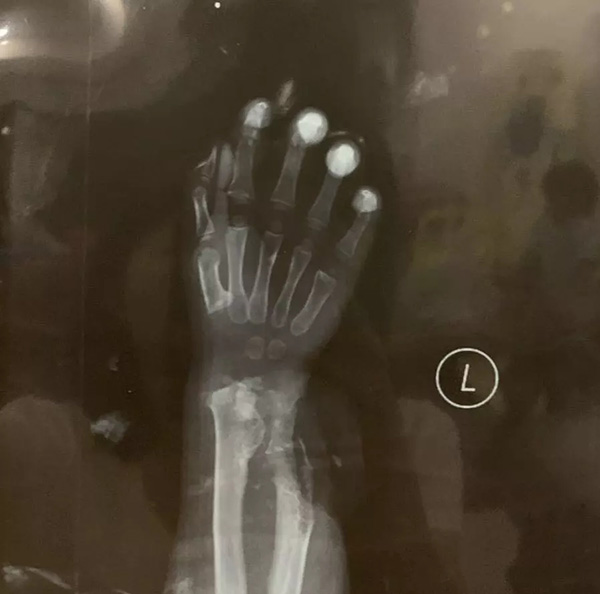

小希希出生后八个月的时候,父母细心地摸到她左手腕有块凸起,肉眼看不出,用力按也不疼,到广州的医院就医确诊为骨软骨瘤,因孩子太小建议每隔半年复查一次。直到2017年初夏,希希手腕的骨软骨瘤越长越大,已经影响到她左手的正常活动。希希父母心急如焚辗转在香港、广州医院求医,医生都建议手术。

希希的父母通过友人介绍北上去了北京积水潭医院小儿骨科看专家,2018年7月,在北京积水潭医院小儿骨科由朱振华主任(教授)成功完成了患腕的手术,当天小希希麻醉醒来,再没打过一次针再没吃过一片药,术后五天希希平稳出院。至今当回忆起那段住院的日子,都让希希的爸妈终身难忘。